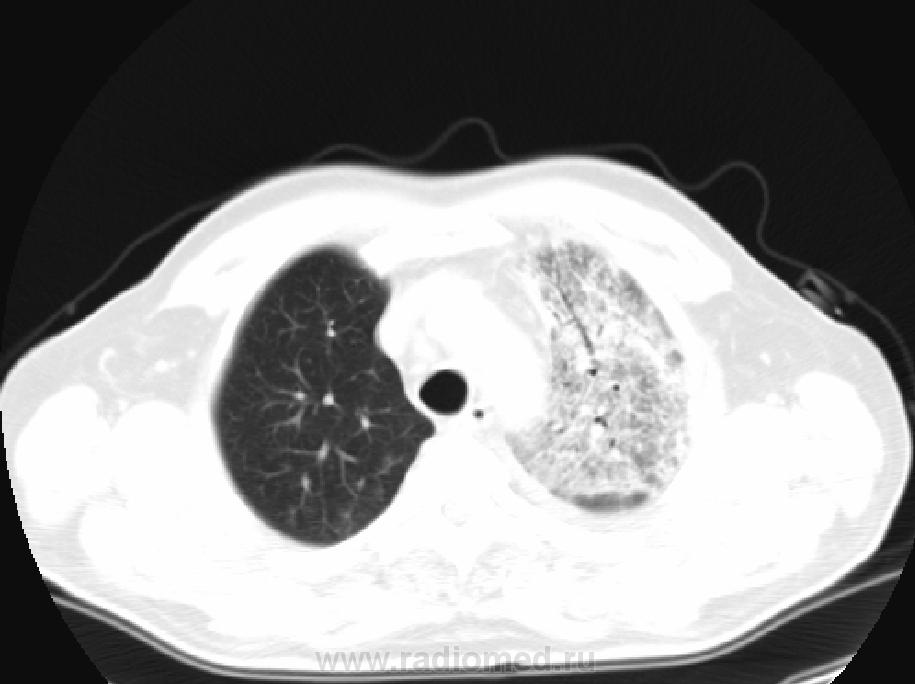

Пацинент 70 лет.  Поступил в терапевтическое отделение 30.12.2011,затем переведен в реанимацию. Заболел остро. Температура тела до 39 С, озноб, ЧДД- 26 в 1 мин. Гемограмма: лейк.14,5*109/л, п/я-24%. лимф.12%. СОЭ - 60 мм/ч. В мокроте сгустки крови. Аускультация - в проекции S1+2  левого легкого многочисленные влажные хрипы (5.1.12). УЗИ сосудов нижних конечностей - норма. Гастроскопия - гастрит. Прошу  Вас коллеги высказать мнение по данному процессу в легких.    Представляю рисунки от 30-31. 2011. КТ от 2.1.2012. Жду. С уважением Nikolas

ИМХО: С учётом всей имеющейся информации больше данных за полисегментарную пневмонию  слева в S1-2 и S2  справа, с относительно быстрой отрицательной динамикой с 30.12.11 на момент 31.12.11г. В диф.ряд можно вынести ТЭЛА, но не уверен, что при инфаркт-пневмонии будет такое острое начало, + отсутствие изменений со стороны вен нижних конечностей, на УЗИ- всё это делает этот DS возможным, но не очень вероятным. Версия БАРа с 2-хстороннней локализацией и таким острым началом, то же не очень убедительна, хотя возможна.

Клебсиелла-пневмония. Пневмонии, вызванные грамотрицательными бактериями из рода клебсиелла, принято разделять на пневмонии с острым началом и обычно молниеносным течением п на пневмонии с постепенным, почти незаметным началом. Острая пневмония (типичная, или фридлендеровская, пневмония) вызывается первыми тремя штаммами рода клебсиелла, рост которых подавляется многими антибиотиками. Другие штаммы этого рода резистентны к большинству антибиотиков. Обычно они оказываются возбудителями пневмонии у хронических больных, получающих длительное время антибиотики. Эта нозокомиальная инфекция начинается обычно незаметно и отличается хроническим течением.

Острая клебсиелла-пневмония начинается всегда внезапно с озноба, болей в боку и кашля. Лихорадка может быть постоянного типа (как при пневмококковой пневмонии) или ремиттирующая; у стариков она может быть умеренной или полностью отсутствовать. Вязкая мокрота с трудом откашливается, по своему виду и консистенции она напоминает черносмородиновое желе. Часто встречается мокрота, представляющая собой желе, окрашенное красной кровью. Примерно в 20% случаев развивается нерезко выраженная желтуха.

Рентгенологическое исследование выявляет гомогенное затемнение большей части или всей доли легкого. Величина и расположение очагов инфильтрации при клебсиелла-пневмонии (как и при пневмококковой) обычно не следуют сегментарному делению легкого. Они располагаются чаще всего в задних отделах верхних долей пли в верхних частях нижних долей легкого. Поражается обычно только одна (чаще верхняя) доля правого легкого.

Снова реинкарнация  случая. Иногда интересно. И несмотря на стафилококк, я вот больше за инфаркт-пневмонию слева в в/доле  выскажусь. Справа тоже характерные для ТЭЛА изменения есть. Короче, за ТЭЛА. Перед Новым годом мне тоже прислали аналогичный случай, острый, правда, буквально за несколько дней деструкция в верхней доле слева образовалась, с кровохарканьем. рентген-картина идентична.